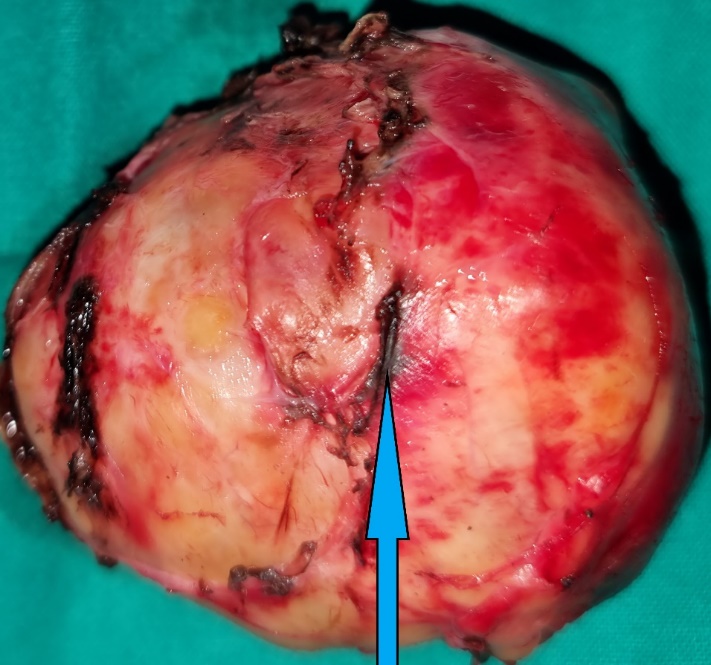

After opening of the specimen, the peripheral solid component and the central cystic component are demonstrated (blue arrow) (Courtesy Dr. V. Penopoulos)